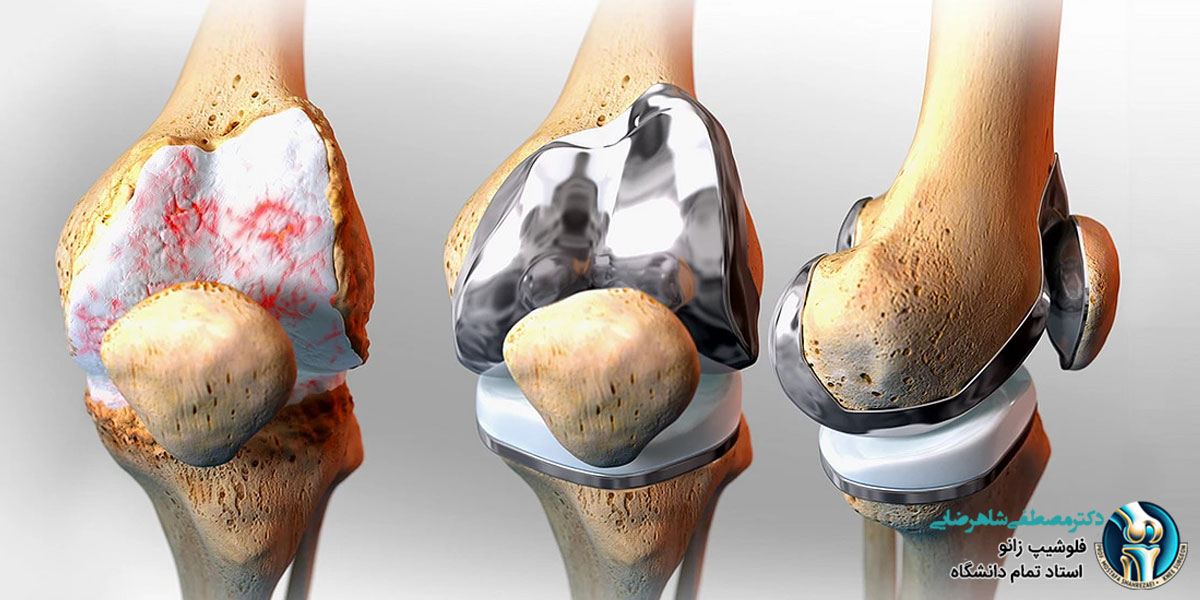

تعویض مفصل زانو به صورت جزئی یا “آرتروپلاستی جزئی زانو” یک روش جراحی است که در آن تنها بخشی از مفصل زانو که آسیب دیده است، جایگزین می شود. این روش در مقایسه با تعویض کامل مفصل زانو تهاجمی کمتری دارد و معمولاً برای افرادی مناسب است که تنها یک قسمت از زانوی آن ها دچار آسیب یا تخریب شده است. در این جراحی، جراح بخش آسیب دیده مفصل را بر می دارد و آن را با یک پروتز مصنوعی جایگزین می کند، در حالی که سایر بخش های سالم زانو دست نخورده باقی می مانند.

تفاوت تعویض مفصل زانو به صورت جزئی و کامل

تفاوت اصلی بین تعویض مفصل زانو به صورت جزئی و کامل در میزان بافت هایی است که در طول جراحی برداشته و جایگزین می شوند. در تعویض کامل مفصل زانو، تمام بخش های مفصل زانو شامل کپسول مفصلی، غضروف ها و حتی رباط ها برداشته می شوند و پروتزهای مصنوعی جایگزین می شوند. این در حالی است که در تعویض جزئی، فقط بخش آسیب دیده مفصل تعویض می شود و بافت های سالم حفظ می شوند. این موضوع نه تنها باعث کاهش زمان بهبودی و درد پس از جراحی می شود، بلکه امکان بازگشت سریع تر بیمار به فعالیت های روزانه را نیز فراهم می کند.

تعویض مفصل زانو به صورت جزئی زمانی انجام می شود که تنها یک بخش از زانو دچار تخریب یا آسیب شده باشد. این روش بیشتر برای بیمارانی که دچار آرتروز موضعی یا پارگی های خاصی در زانو هستند مناسب است. از جمله شرایطی که ممکن است نیاز به تعویض مفصل زانو به صورت جزئی باشد عبارتند از:

- آرتروز یک طرفه زانو: این نوع آرتروز معمولاً یک سمت از مفصل زانو را تحت تأثیر قرار می دهد. در این حالت، تعویض جزئی مفصل زانو می تواند راه حل مناسبی باشد.

- آسیب موضعی به غضروف: در صورتی که تنها غضروف یک بخش از زانو دچار آسیب شده باشد، تعویض جزئی می تواند به حفظ سایر بخش های سالم زانو کمک کند.

- پارگی منیسک یا رباط های داخلی زانو: در مواردی که پارگی منیسک یا رباط ها به حدی نیست که نیاز به تعویض کامل مفصل باشد، تعویض جزئی می تواند موثر باشد.